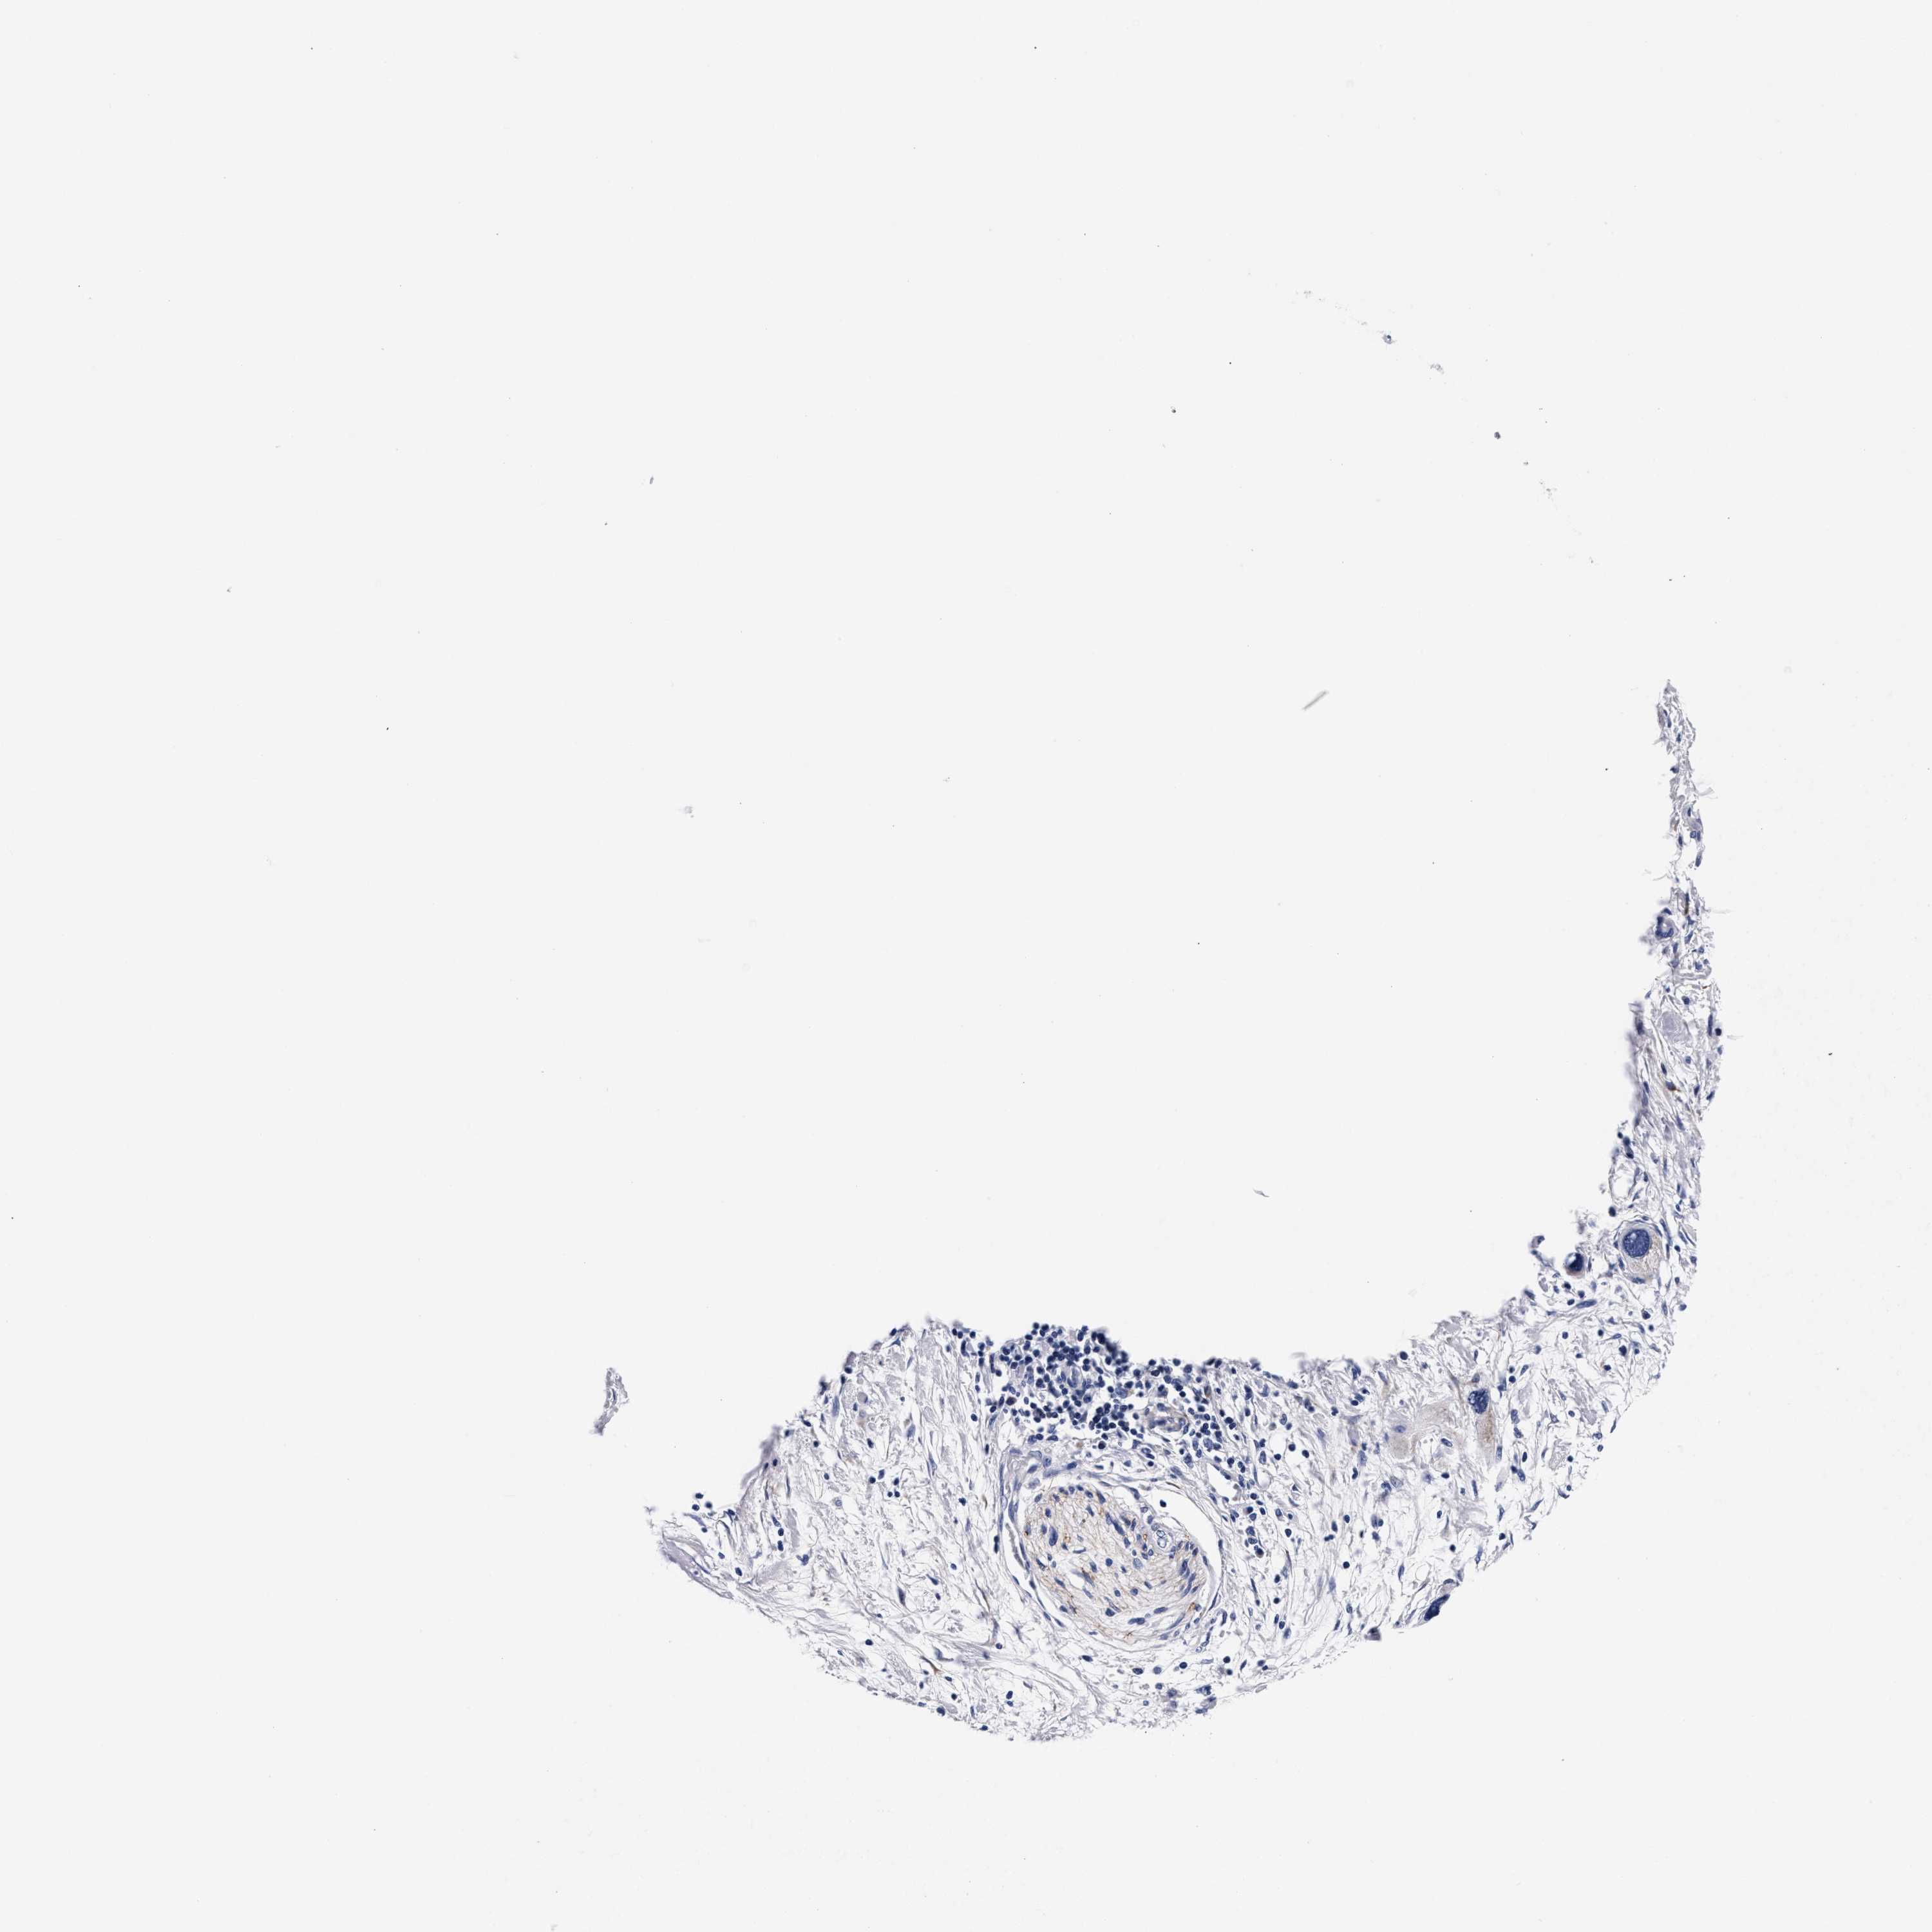

PANCREATIC CANCER - Protein expressioni

A mouse-over function shows sample information and annotation data. Click on an image to view it in a full screen mode. Samples can be filtered based on level of antibody staining by selecting one or several of the following categories: high, medium, low and not detected. The assay and annotation is described here.

Note that samples used for immunohistochemistry by the Human Protein Atlas do not correspond to samples in the TCGA dataset.

Antibody stainingi

Antibody staining in the annotated cell types in the current human tissue is reported as not detected, low, medium, or high, based on conventional immunohistochemistry profiling in selected tissues. This score is based on the combination of the staining intensity and fraction of stained cells.

Each image is clickable and will lead to virtual microscopy that enables deeper exploration of all samples and also displays staining intensity scores, fraction scores and subcellular localization as well as patient and tissue information for each sample.

Antibody HPA003159

Antibody CAB023293

Adenocarcinoma, NOS

Adenocarcinoma, metastatic, NOS